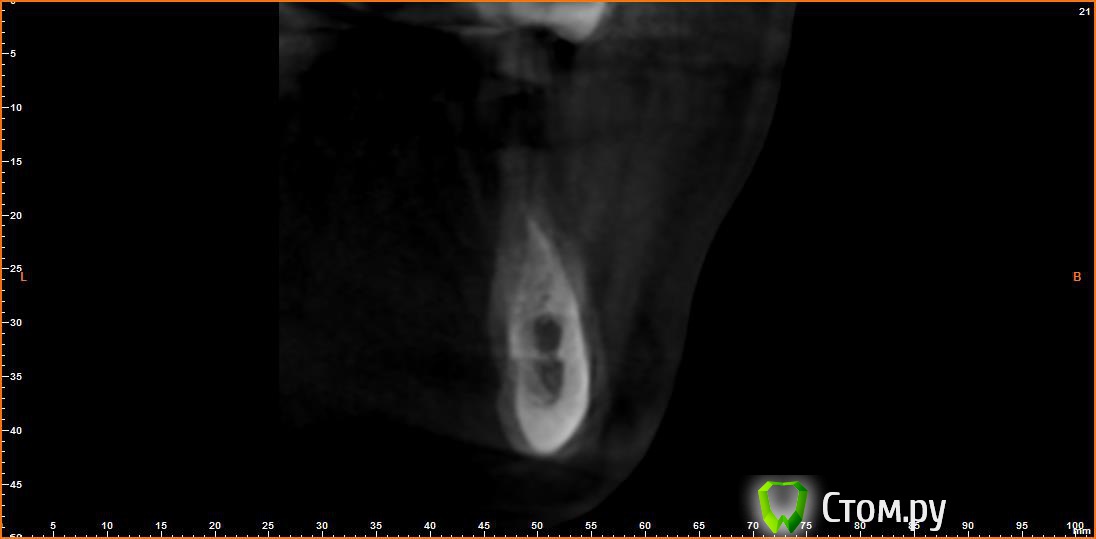

Opimar Опубликовано 21 июня, 2014 Автор Поделиться Опубликовано 21 июня, 2014 Выкладываю еще. Пошагово от 34-37 Ссылка на комментарий

Bier Опубликовано 21 июня, 2014 Поделиться Опубликовано 21 июня, 2014 Выкладываю еще. Пошагово от 34-37темная точка достаточно высоко, это по моему не нерв, нерв ниже, я правильно понимаю? Ссылка на комментарий

Opimar Опубликовано 21 июня, 2014 Автор Поделиться Опубликовано 21 июня, 2014 темная точка достаточно высоко, это по моему не нерв, нерв ниже, я правильно понимаю?Да он ниже и язычнее. Провел от менталиса там еще запас есть. Ссылка на комментарий